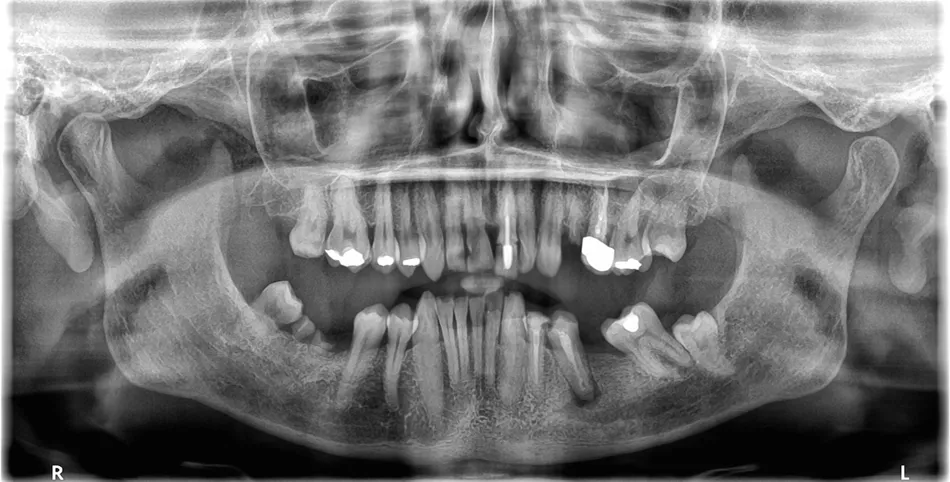

A 64-year-old male patient, in good general health, presented to our clinic with partial edentulism associated with compromised aesthetics, and impaired masticatory function. The patient expressed dissatisfaction with his smile and reported difficulty chewing due to multiple missing teeth.

Clinical and radiographic findings revealed missing teeth, failing prosthetic restorations, and chronic odontogenic infections, collectively contributing to functional impairment which negatively impacted the patient’s self-esteem and overall well-being, leading them to seek comprehensive implant-based rehabilitation. Given the patient’s clinical presentation and functional needs, a digitally driven rehabilitation pathway was selected to leverage the efficiency and predictability of current digital implant ecosystems. Contemporary digital workflows provide improved diagnostic accuracy, streamlined communication, and more predictable restorative outcomes compared with analogue approaches [1]. The integration of virtual planning, CAD/CAM‑guided surgery, and scannable anatomical healing abutments aligns with evidence demonstrating enhanced precision, reduced technique sensitivity, and better intraoral scanning fidelity in implant‑supported rehabilitation. Collectively, these advancements made the digital pathway the most seamless and biologically favourable treatment choice for this case [2].

1. Panoramic view showing severe bone loss around tooth 15, confirming hopeless prognosis.